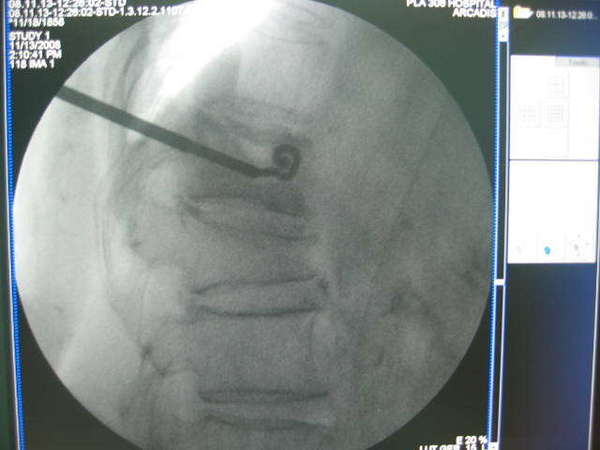

治疗----后路经皮穿刺、球囊扩张、椎体成型术

比较手术前后显示T12骨折椎体高度恢复,脊柱后凸畸形获得明显改善,填充骨水泥到位并均匀,无渗漏现象.